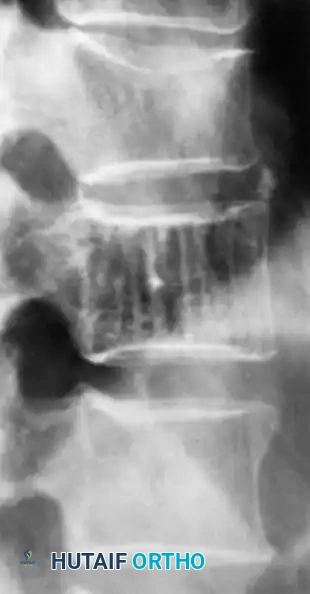

Fig. 20-20: Lateral radiograph of the lumbar spine demonstrating the typical “jailhouse” appearance of a vertebral hemangioma, characterized by prominent vertical trabecular striations.

The radiographic signature in the spine is highly characteristic. Resorption of horizontal trabeculae combined with compensatory thickening of vertically oriented trabeculae produces the classic "jailhouse" or "corduroy cloth" appearance. On axial CT imaging, these thickened trabeculae manifest as a distinct "polka dot" pattern. MRI is definitive; the lesions are typically hyperintense on both T1- and T2-weighted images due to the presence of intralesional fat and slow-flowing blood.